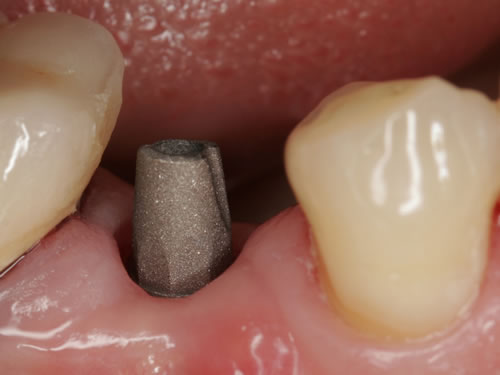

Abb. 8.26: Kronenpfosten vor Eingliederung der Implantatkrone.

Abb. 8.27: Perfektes Ergebnis einer Einzelkrone eines oberen seitlichen Schneidezahnes.